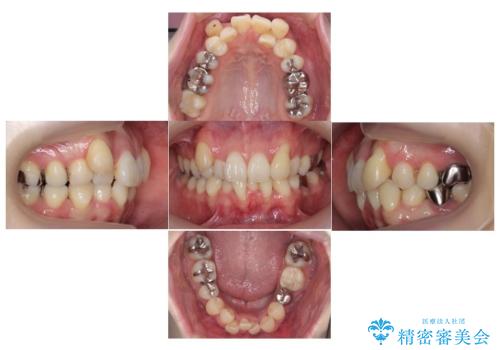

全体的な虫歯治療 銀歯をセラミックに

- 当院で矯正治療後、虫歯治療を一通り行いました。

矯正治療後はリテーナーを使用する必要がありますが、両方同じ病院で行うことにより、リテーナーの再作成や修理もしっかり対応できます。